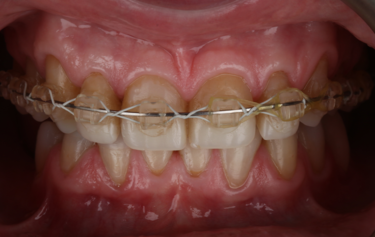

Figure 2: Frontal retracted view – before

Her main concern was the size discrepancies and tooth wear that was obvious within her smile. She had a low lip line and slightly deficient buccal corridors (Fig. 1). She was posturing into a pseudo-class 3 occlusion with passive overeruption of all her teeth, more noticeable on the anterior upper and lower labial segment (Fig. 2). She had missing posterior teeth and so all her mastication was on a reduced dental arch.

Her teeth showed tooth surface loss and passive eruption of the both the upper and lower anterior segment with excessive upper gum on show during forced wide smiling. The diagnosis of severe attrition and tooth surface loss was made, as a result of previous acidic reflux, stress-related parafunction, and a highly acidic diet, which lead to the erosion and subsequent collapse of the arches and loss of occlusal-vertical dimension.